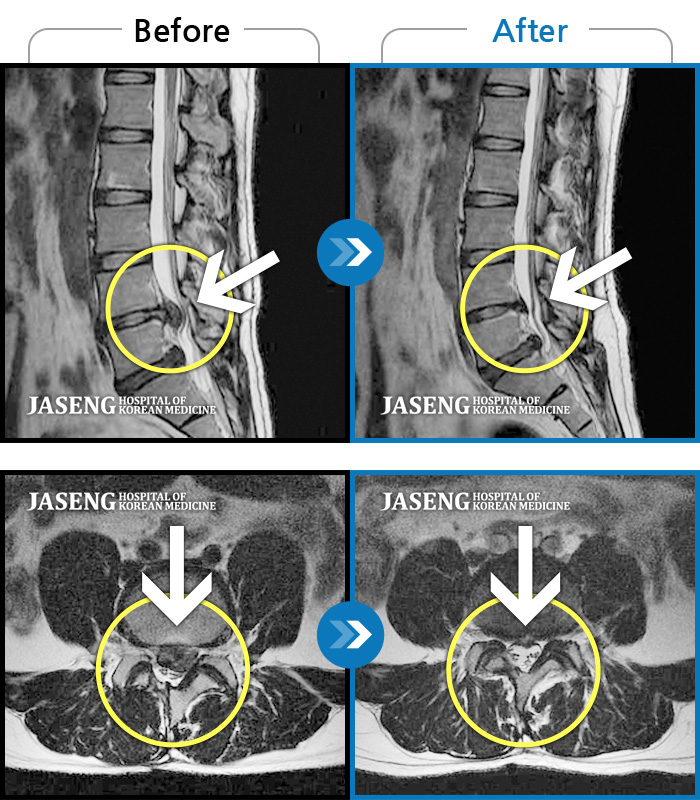

허리디스크

잠실 · 한상욱 원장

허리가 많이 아프고 왼쪽 다리가 저려 움직이기가 힘들다.

촬영시기

2022.01.19 ~ 2022.11.14

2022.12.02